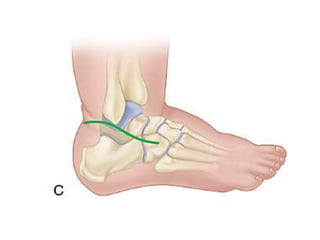

Mid foot score

• Talar head coverage [C]

Mid foot score •Curved lateral border [A] • Medial crease [B] • Talar head coverage [C]